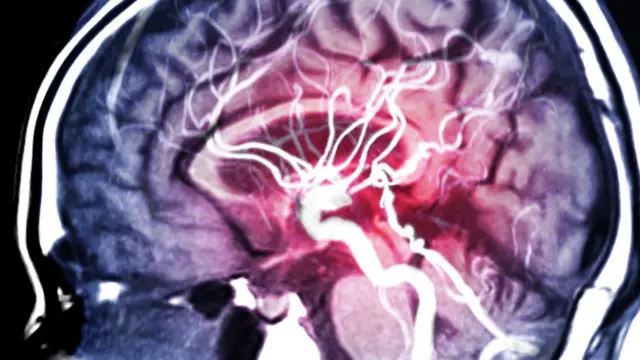

Segundo o médico neurologista, o aneurisma cerebral é uma dilatação dos vasos sanguíneos, causada por uma fraqueza na parede do vaso.

"O vaso é constituído por uma camada de músculo e em regiões onde há fraqueza dessa camada muscular pode-se desenvolver uma dilatação, algo semelhante a uma bolha ou um balão de ar", explica. "Se essa fraqueza progride pode haver a ruptura do vaso, causando uma hemorragia cerebral ou, como chamamos na área médica, um AVC hemorrágico". Aneurisma cerebral: condição que ex-BBB Juliette achava ter pode ser genética?